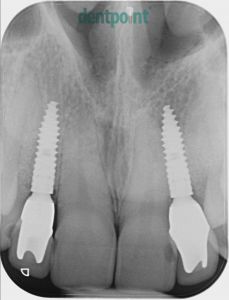

Régi implantátumok cseréje, fémmentes koronák felhelyezése

Fiatal hölgy páciensünk a 10 évvel ezelőtt behelyezett implantátumainak csontpusztulása és ínyének visszahúzódása miatt keresett fel minket. A régi implantátumok eltávolítását követően újakat helyeztünk be, és ínyplasztikai kezeléssel, valamint cirkónium egyéni implantátum fejekre készített e.max fémmentes kerámia koronákkal adtuk vissza páciensünk elégedett mosolyát.

Implantáció, fogpótlások: Dr. Molnár Bálint

1) Kiindulási helyzet

2) Implantátumok és koronák cseréje után

1) Kiindulási helyzet röntgenfelvétel

2) Implantátumcsere utáni röntgenfelvétel